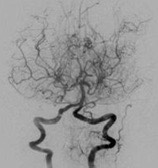

모야모야병은 뇌혈관, 특히 뇌로 혈액을 공급하는 내경동맥과 그 주변 주요 혈관이 점점 좁아지고 막히는 희귀 난치성 질환으로, 혈류가 줄어든 뇌는 부족한 혈액을 보충하기 위해 가느다란 미세측부혈관들을 새로 만들어냅니다. 이 작은 혈관들이 연기처럼 보인다고 하여 일본어로 ‘모야모야(안개·연기)’라는 이름이 붙었습니다. 소아부터 성인까지 폭넓게 나타나며, 특히 5~10세 어린이와 30대 전후의 여성에서 비교적 많이 발견되는 경향이 있습니다. 증상은 일시적 마비, 언어장애, 두통, 실신, 경련 등 매우 다양해 뇌졸중과 유사하거나 초기에는 가벼운 신경학적 증상으로만 나타나 진단이 늦어지기도 했습니다. 질환이 진행하면 허혈성 뇌졸중(뇌경색)이나 출혈성 뇌졸중 위험이 증가하여 반드시 전문적인 관리가 필요합니다. 아직 완전히 예방할 수 있는 방법은 없지만 조기 진단과 적절한 치료를 통해 뇌 기능을 보호하고 삶의 질을 유지할 수 있습니다.

모야모야병은 뇌기저부의 주요 혈관이 서서히 협착되고 막히면서 뇌혈류가 감소하는 만성 진행성 뇌혈관 질환입니다. 협착이 진행된 부위를 대신해 뇌는 생존을 위해 얇고 약한 혈관망을 만들어 혈류를 보충하려 하고, 이 새로운 혈관들이 촬영 영상에서 연기처럼 퍼져 보인다고 하여 ‘모야모야’라는 이름이 붙었습니다. 기전적으로는 내경동맥 말단부와 중대뇌동맥·전대뇌동맥의 기시부에 병변이 가장 잘 생기며, 시간이 지남에 따라 양쪽에 대칭적으로 나타나는 특징을 보였습니다. 이 질환은 단순한 혈관 협착이 아니라 진행성 변화이기 때문에 치료하지 않으면 혈류 부족이 심해지고 뇌 손상이 누적될 수 있습니다. 또한 뇌기능이 체력·호흡·체온 변화 등에 민감하게 반응하기 때문에 과호흡, 울음, 격렬한 운동, 감염 등으로 증상이 악화될 수 있습니다. 즉, 모야모야병은 시간이 지나면서 뇌혈류를 감소시키고 뇌졸중 위험을 높이는 질환이며, 평생 관리가 필요한 만성적 특성을 갖고 있습니다.